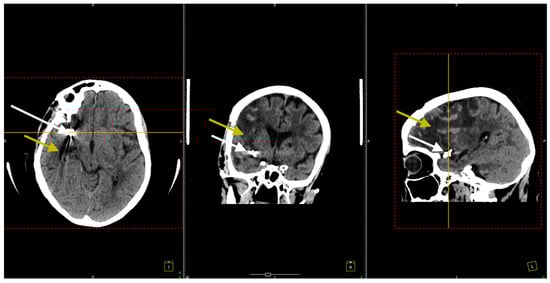

At her 3-month follow-up check, a repeat native cerebral CT scan was conducted (Figure 7).

Figure 7. The CT scan conducted 3 months after the surgical procedure. All three sections, transversal (left image), coronal (middle image), and sagittal (right image), confirmed the right frontotemporal hypodensity consistent with ischemic stroke (yellow arrows) and noted artifacts from the previously placed aneurysm clips (white arrows).